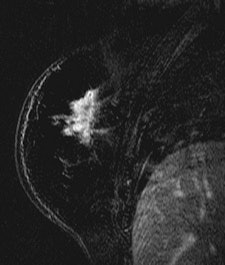

| Patient with breast cancer (invasive ductal carcinoma, grade II). MR-subtracted images (three minutes after contrast medium injection) before (left) and at the end (right) of the neoadjuvant chemotherapy. Initial staging: unifocal infiltrating cancer. After treatment, even if there is a decrease in size of the cancer, its long axis (RECIST) is unchanged with a multifocal shrinkage of the tumor. Unsuccessful first breast-conserving surgery, then mastectomy. Image courtesy of Dr. Anne Tardivon. |